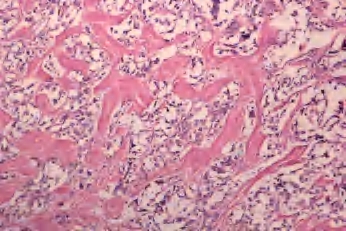

(2)大滤泡亚型:罕见,主要或全部由大滤泡构成,常与增生性结节或大滤泡腺瘤混淆;但滤泡细胞含有大而亮的核和核沟、核内假包涵体。此亚型很少见到淋巴结转移(图3-46、图3-47)。

图3-46 甲状腺乳头状癌,大滤泡亚型

图3-47 甲状腺乳头状癌,大滤泡亚型